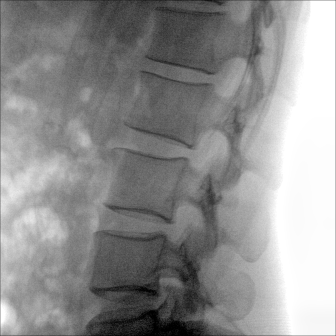

大尺寸動態(tài)平板探測器,高DQE、低噪聲、圖像清晰。采用多分辨率圖像增強(qiáng)處理技術(shù),不同部位不同圖像處理算法,滿足客戶多樣化的需求。

采用智能變頻脈沖透視技術(shù),優(yōu)化圖像質(zhì)量的同時降低輻射劑量,呵護(hù)醫(yī)患健康